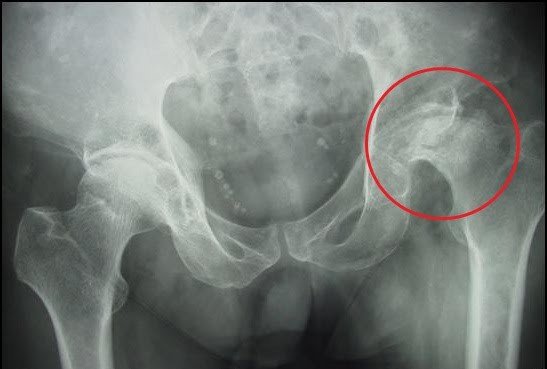

Hoại tử chỏm xương đùi hay còn gọi là hoại tử vô mạch chỏm xương đùi, nguyên nhân do thiếu máu nuôi dưỡng. Dẫn tới tình trạng xương hoại tử tổ chức xương và sụn, lúc đầu vùng chỏm xương thưa dần, hình thành các ổ khuyết xương về sau dẫn tới gãy xương dưới sụn và cuối cùng gây ra xẹp chỏm xương đùi, mất chức năng khớp háng dẫn đến tàn phế.

Hình ảnh: Hoại tử chỏm xương đùi

- X quang: Bao gồm phim chụp X quang khớp háng thẳng và nghiêng, xquang khớp háng kiểu đùi chếch là phương tiện đầu tiên được lựa chọn để chẩn đoán hoại tử chỏm xương đùi.

Hình ảnh: Nhẹ thấy hình ảnh xương thưa, thường thấy xẹp chỏm từ nhẹ đến nặng, nặng nhất là thấy mất một phần hoặc hoàn toàn chỏm, hình ảnh hẹp khe khớp.

Hình ảnh hoại tử chỏm xương đùi qua phim chụp Xquang